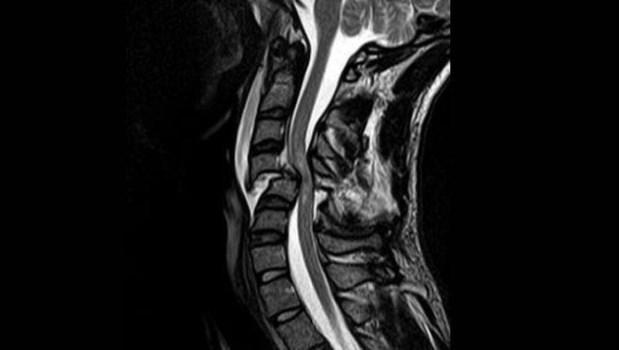

Los traumatismos, ya sea por deportes o por accidentes de tránsito, son la principal causa de las lesiones medulares en pacientes jóvenes, mientras que en los adultos éstas también pueden ocurrir por artrosis (cuando se estrecha el canal medular en la columna cervical, por ejemplo), hernias de disco o también tumores.

Cuando ocurren por golpes es importante realizar estudios neurofisiológicos ni bien el paciente llega al hospital, porque con esa información se marcará el curso de acción a seguir. En concreto, no pueden faltar los potenciales evocados somatosensitivos (SSEP), que evalúan la transmisión nerviosa de los impulsos en las vías somatosensoriales de las extremidades (superior e inferior) y en el cerebro, y se pueden utilizar para diagnosticar las lesiones a nivel de las raíces nerviosas, la médula espinal y el cerebro.

Es importante que se pidan estos estudios y no quedarse solo con la resonancia. Para explicar cómo se complementan ambos exámenes suelo elegir la metáfora de la pared de una casa. La resonancia equivaldría a fotografiar una mancha de humedad, mientras que los potenciales evocados somatosensitivos equivaldrían a la visita del electricista para revisar el “cableado” que pasa a través de ella.

Con los SSEP se evalúa la función de la médula espinal propiamente dicha: se confirma si la transmisión de los impulsos ocurren aún tras una lesión o un estrechamiento del canal. Estas pruebas pueden complementarse con la electromiografía, que analiza la actividad eléctrica de los músculos y los nervios y con el estudio de los reflejos medulares.